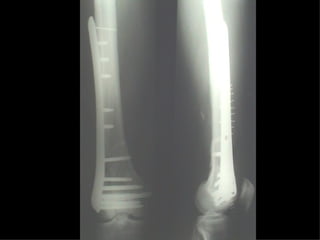

Dal Gennaio 2000 al Febbraio 2006 abbiamo trattato 167 fratture chiuse  con placca percutanea  in 164 pazienti :  27 lesioni diafisarie di gamba, 12 piloni tibiali ,  11 fratture prossimali di tibia, 36 fratture sovracondiloidee di femore, 17 fratture diafisarie di femore, 43 fratture metaepifisarie prossimali di omero, 21 diafisarie d’omero.  156 guarigioni 8 fallimenti

Dal Giugno 2002 al Dicembre 2004 abbiamo trattato 5 fratture esposte: 3 di tibia e 2 di ulna 5 guarigioni

I buoni risultati ottenuti dipendono da 5 punti fondamentali:   una accurata riduzione percutanea della frattura  precise vie di accesso  l’utilizzo della placca che consenta il più lungo braccio di leva possibile il pretensionamento della placca  una sintesi con un ridotto numero di viti

Fratture  esposte